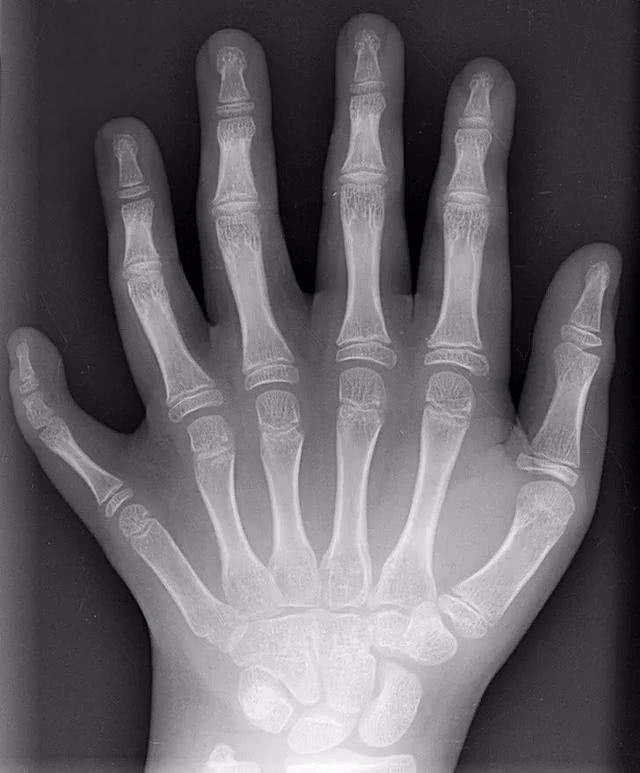

做了有辐射的检查是不是会得肿瘤?我们说要尽量避免接受有辐射的检查 , 当然是要避免其危害 。 接受过辐射检查的次数越多、受到辐射的剂量越大 , 出现辐射危害的风险当然也越大 。 但是 , 由于近年来在设备低剂量技术的进展以及辐射防护认识上的提高 , 已经多年来没有出现过有接受辐射检查而罹患肿瘤的病例报道了 。 如果有意去检测设备和检查的辐射剂量 , 也基本上不会超过国家的规定范围 。 而危害最大的 , 反而是有些人“患得患失”整天提心吊胆所引起的心理伤害 。 所以 , 我有必要提醒:在检查前 , 医患双方必须评估检查的必要性;检查后 , 完全没有必要在是否有伤害、是否会引起癌症等方面继续担忧 。